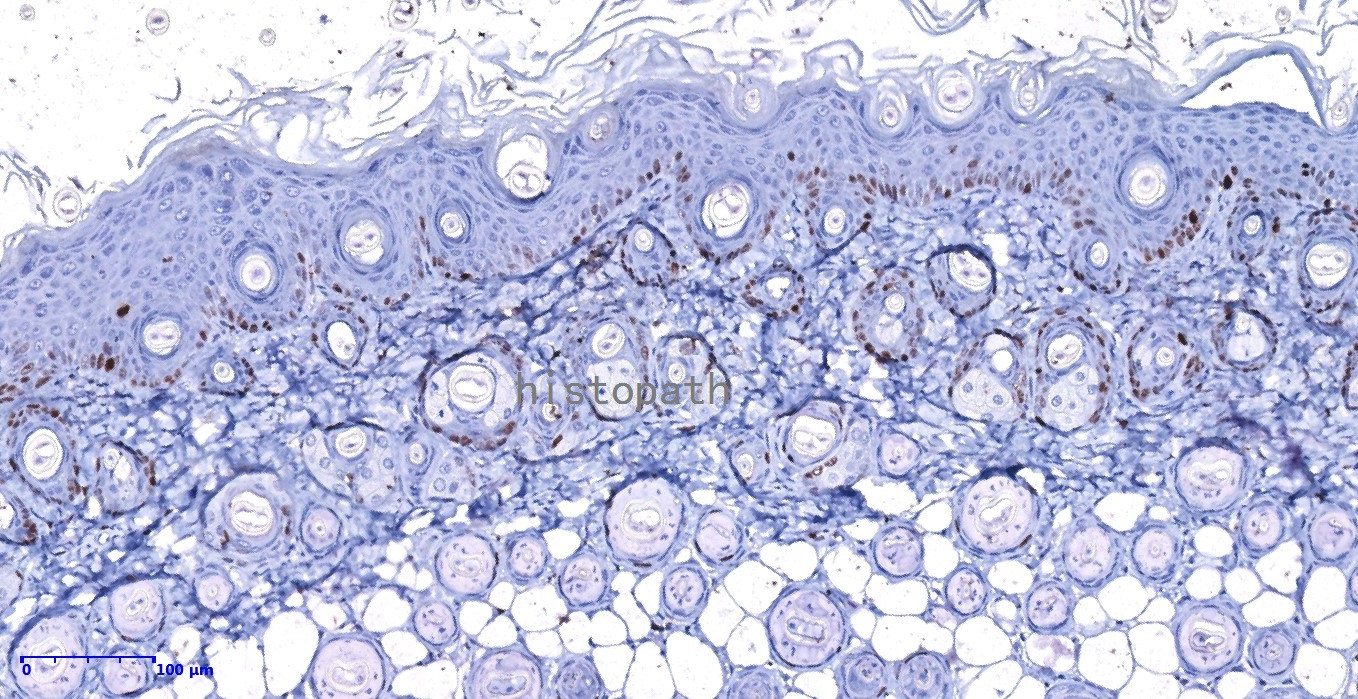

免疫组化:

是应用免疫学基本原理——抗原抗体反应,即抗原与抗体特异性结合的原理,通过化学反应使标记抗体的显色剂(荧光素、酶、金属离子、同位素)显色来确定组织细胞内抗原(多肽和蛋白质),对其进行定位、定性及定量的研究,称为免疫组织化学技术(immunohistochemistry)或免疫细胞化学技术(immunocytochemistry)。

8, 显色:DAB显色液,配置DAB:1mlB液+1滴A液混匀,滴加DAB显色液,镜下观察至阳性明显增强、背景干净终止显色;如果显色淡,可重复上一步增强显示色。

结果:阳性部位棕褐色,细胞核天蓝色,对比鲜明,无背景着色。